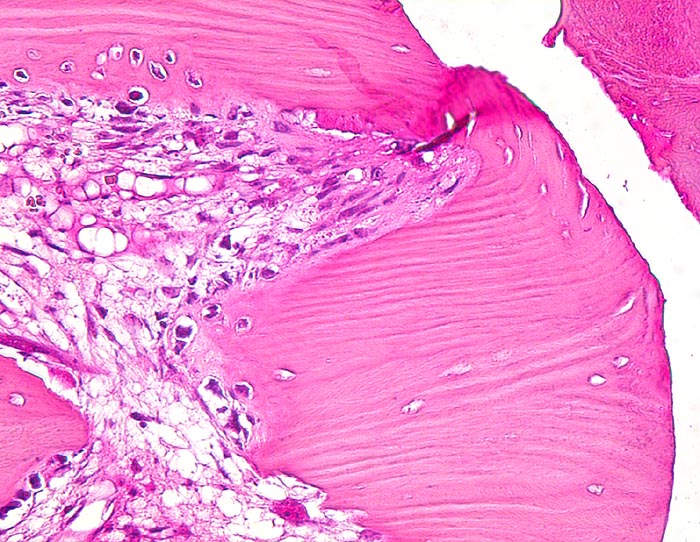

Morphologische Merkmale:

• Verschiebung der Bruchstücke gegeneinander.

• Über dem Frakturspalt senkrecht auf die Frakturlinie ausgerichtete Faserknochenbälkchen mit Osteoblastensaum und ausgedehnte Bezirke von neugebildetem Knorpel.

• Devitalisierter ortsständiger Knochen mit leeren Osteozytenhöhlen angrenzend an den Frakturspalt.

• Knochenmark zu beiden Seiten der Frakturlinie mit Markfibrose.

• Fibrinablagerung und Knorpelneubildung im Frakturspalt.

• Enchondrale Ossifiktation des neugebildeten Knorpels.

• Auch entfernt von der Bruchlinie Neubildung von Knochenbälkchen im Markraum.